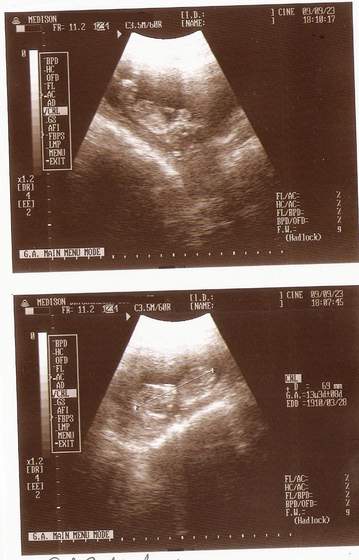

A pierwsze poczułam na uczeli idę sobie prze korytarz i takie bulgotanie poczułam i jkaby ktoś się "zamachnął", ale tak mnie wryło w podłogę, ze aż mi książki spadły.